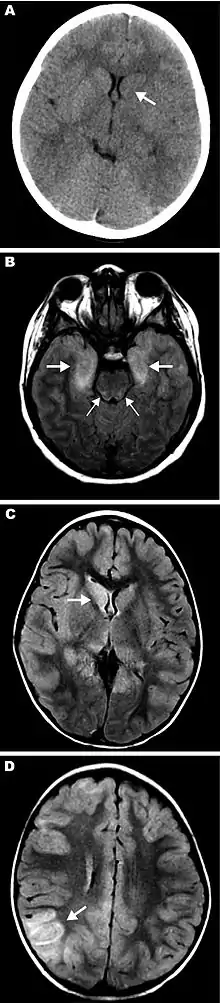

Eastern equine encephalitis (EEE), commonly called Triple E or sleeping sickness (not to be confused with African trypanosomiasis), is a disease caused by a zoonotic mosquito-vectored Togavirus that is present in North, Central, and South America, and the Caribbean. EEE was first recognized in Massachusetts, United States, in 1831, when 75 horses died mysteriously of viral encephalitis. Epizootics in horses have continued to occur regularly in the United States. It can also be identified in donkeys and zebras. Due to the rarity of the disease, its occurrence can cause economic impact beyond the cost of horses and poultry.[2] EEE is found today in the eastern part of the United States and is often associated with coastal plains. It can most commonly be found in East Coast and Gulf Coast states.[1] In Florida, about one to two human cases are reported a year, although over 60 cases of equine encephalitis are reported. In years in which conditions are favorable for the disease, the number of equine cases is over 200.[3] Diagnosing equine encephalitis is challenging because many of the symptoms are shared with other illnesses and patients can be asymptomatic. Confirmations may require a sample of cerebral spinal fluid or brain tissue, although CT scans and MRI scans are used to detect encephalitis. This could be an indication that the need to test for EEE is necessary. If a biopsy of the cerebral spinal fluid is taken, it is sent to a specialized laboratory for testing.[4]

- ↑ Deresiewicz RL, Thaler SJ, Hsu L, Zamani AA (1997). "Clinical and neuroradiographic manifestations of eastern equine encephalitis". N. Engl. J. Med. 336 (26): 1867–74. doi:10.1056/NEJM199706263362604. PMID 9197215.